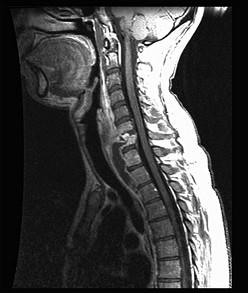

问题 男,38岁,颈部疼痛伴低热1月余,曾有结核病史,结合MRI图像,最可能的诊断是 ( )

选项 A、颈椎骨转移瘤 B、食管异物并感染 C、颈椎体结核 D、咽后脓肿 E、颈椎体结核及咽后脓肿

答案 E